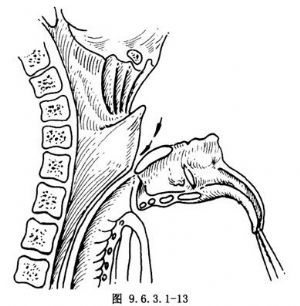

(7)切斷氣管取出喉體:在環狀軟骨下緣切斷氣管直達氣管後壁(圖9.6.3.1-13),沿氣管食管壁之間分離,喉體即可取除。如欲保留環狀軟骨,可在環狀軟骨上緣切開向後達環狀軟骨板水平切斷,同時切開環後板後面的黏膜與兩側梨狀窩切口相連,喉體即可取除。